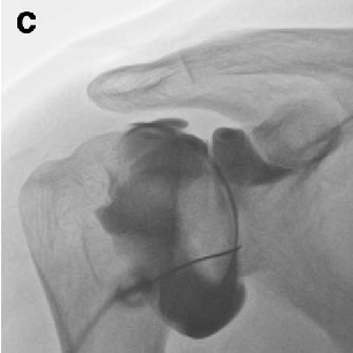

오십견의 치료

관절 가동 범위를 확대하기 위해 관절낭 팽창술과 함께 인대강화주사를 할 수 있으며 이 후 재활기간 동안 어깨관절도수를 시행하게 됩니다. 심각한 오십견의 경우 어깨부위를 마취하고 수동 조작을 통해 어깨 관절 가동범위를 정상화 할 수 있습니다.